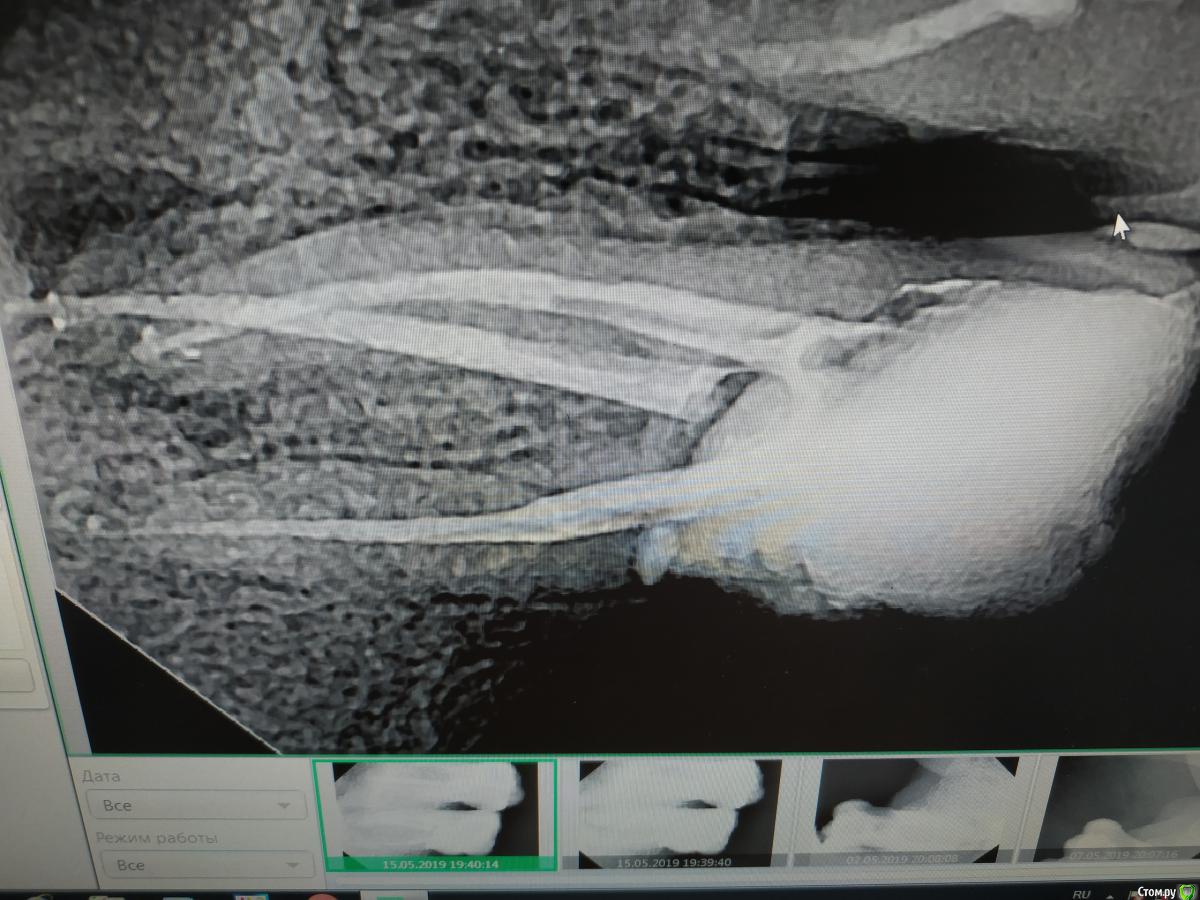

4.6 - острый пульпит. В дистальном 25.04, в медиальных 20.02. Не смог обработать до большего, да и не увидел в этом смысла. В дистальном я силер не выводил, он сам))

Просто несколько работ, достаточно рутинных